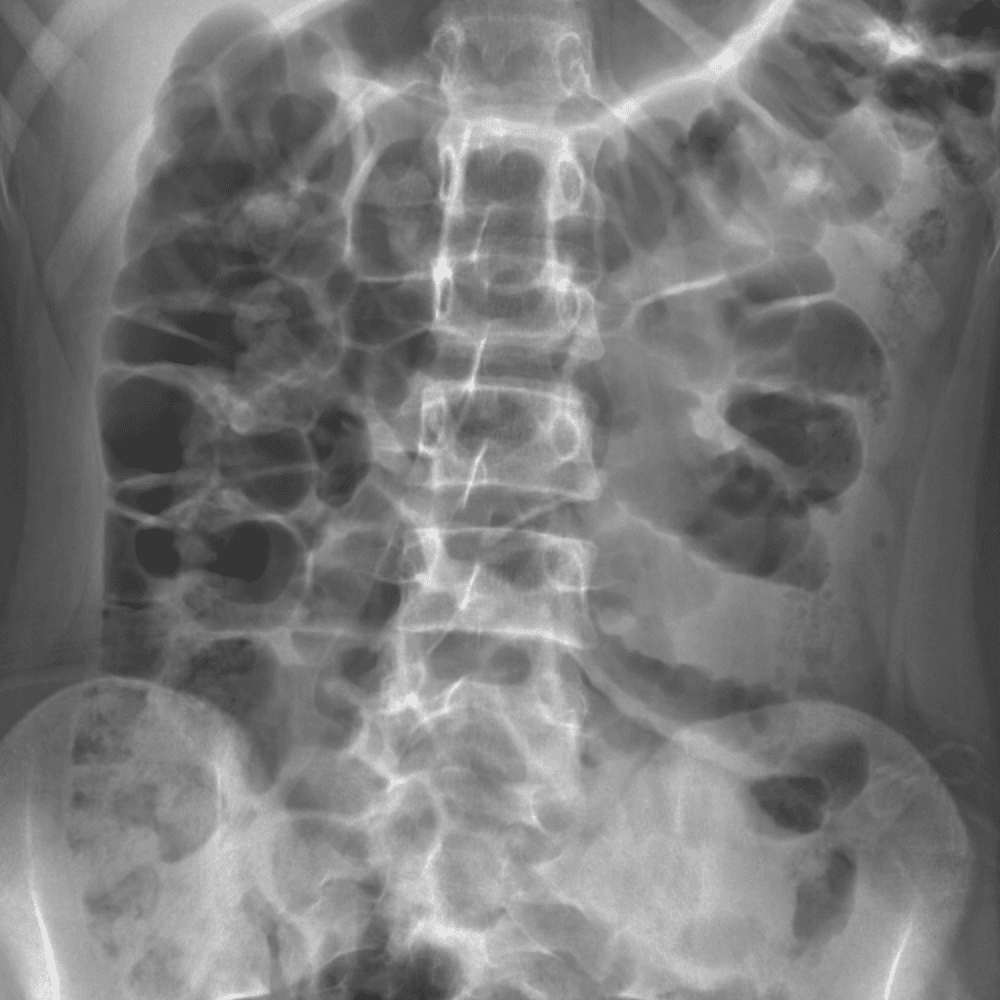

Peds Abdomen

Practice

Simulates call by including subtle or difficult cases and some normals.

30 cases